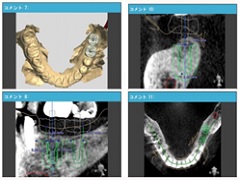

② PCシュミレーション

PCによる「シュミレーション手術」を元に、インプラントの最適な手術位置を設定し、実際の手術が行うことが可能です。また、それぞれの患者様に最適なサージカルプレートを製作致します。